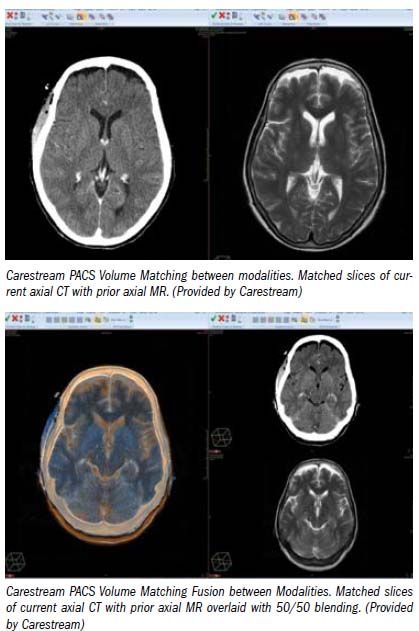

This a perfect place to use the thin slices of the CT scan, the ones that are too thin to be viewed individually, to reslice that data so the two scans line up with each other in 3D space: the nose in one scan points in exactly the same direction as in the other. For the first time, we can really compare two different scans matched up exactly, slice by slice, even though their orientations in 3D space were different at the time of acquisition.

With this foundation, new kinds of comparisons can be made that were previously impossible. Not only can the matched slices be compared side by side, they can even be overlaid on each other with different color maps. And a slider bar can be used to transition the opacity/transparency of one scan or the other, back and forth, to truly see if a brain tumor or lung nodule or kidney mass has changed in size.

Such overlays just never made sense before because the slices of two scans never really matched up with each other. This kind of image registration can be performed not only between two scans from the same modality, but with any other volumetrically acquired modality as well, such as PET or MRI. So a preoperative CT scan, for example, can be directly overlaid on a postoperative MRI.